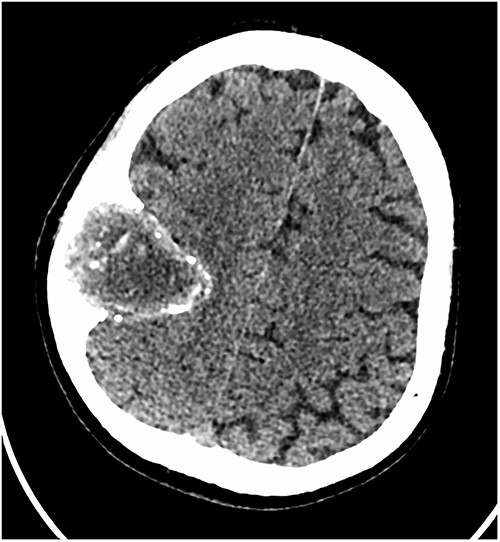

Our patient is a 76-year-old gentleman with medical history of hypertension and lumbar spondylosis. He did not have any previous history of trauma or systemic infections. He had presented to his local hospital with a 2-day history of left arm numbness. He did not report any headaches or giddiness. On clinical assessment, he did not have any neurological deficits. A CT brain and MRI brain (Figs 1–5) with contrast revealed a 53 × 53 × 41 mm partially calcified, heterogeneously enhancing conical shaped right extra-axial parietal convexity lesion. The overlying calvarial bone was remodelled and possibly eroded. There was evidence of prior haemorrhage within the lesion and scattered internal and peripheral calcification. Based on these characteristics, the possible diagnoses were that of an intraosseous meningioma, haemangioma and giant cell tumour. Patient was consented for craniotomy and excision of the tumour.

Axial CT scan showing the extra-axial lesion with surrounding bone remodelling.